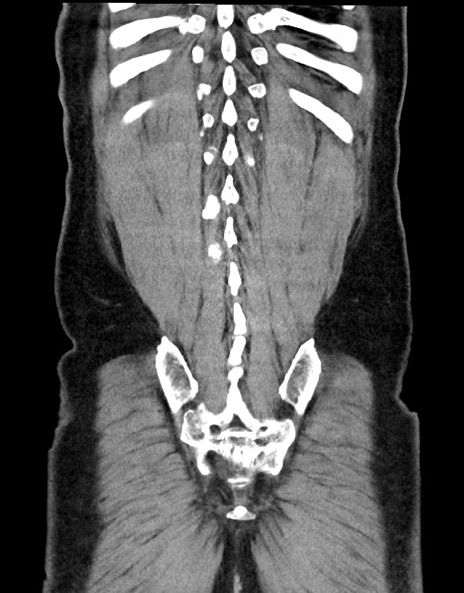

症例15(冠状断像)

症例

【症例】70歳代男性

【主訴】腹痛

【現病歴】今朝から腹痛あり。全体的に痛い。特に左上の方。排ガスが今日はない。冷や汗が出る。

【既往歴】直腸癌術後

【身体所見】左側腹部〜上腹部に圧痛あり。腹膜刺激症状明らかなではない。軽度反跳痛。左下腹部に術後瘢痕あり。

【データ】WBC 7700、CRP 0.02

横断像